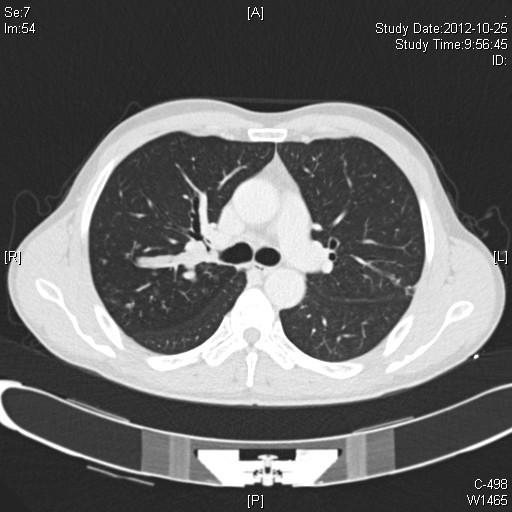

This report describes a case report of a minimally invasive technique for VATS right upper sleeve lobectomy with a two-port approach. To our knowledge it is the first report of this kind. A 50-year-old man with a pulmonary nodule occluding the orifice of the right upper lobe bronchus was referred to our department. Dissection, stapling the right upper lobe pulmonary vessels and anastomosis between the right intermediate and the right main bronchus were performed via the two port. To deal with blocking of pulmonary artery and obtain a satisfactory exposure and manipulating space in the course of bronchial anastomosis were the key points. Intraoperative blood loss was 150 ml and total operative time was 220 minutes. The postoperative course was uneventful. Chest X-rays showed no sign of atelectasis. Postoperative histopathological examination revealed that the tumor was T3N0M0 squamous cell carcinoma. The patient was discharged from hospital on postoperative day 9 without any complications. We conclude that video-assisted thoracoscopic sleeve lobectomy with mediastinal dissection by two-port approach is feasible and convenient.

本报告描述了一例采用双孔入路的电视辅助胸腔镜手术(VATS)右上叶袖式肺叶切除术的病例报告。据我们所知,这是此类的首例报告。一名50岁男性因肺结节阻塞右上叶支气管开口而转诊至我科。通过双孔进行了解剖、缝合右上叶肺血管以及右中间支气管与右主支气管之间的吻合。处理肺动脉阻塞并在支气管吻合过程中获得满意的暴露和操作空间是关键要点。术中失血150毫升,总手术时间为220分钟。术后病程顺利。胸部X线片显示无肺不张迹象。术后组织病理学检查显示肿瘤为T3N0M0鳞状细胞癌。患者术后第9天出院,无任何并发症。我们得出结论,通过双孔入路进行电视辅助胸腔镜袖式肺叶切除术并进行纵隔解剖是可行且方便的。